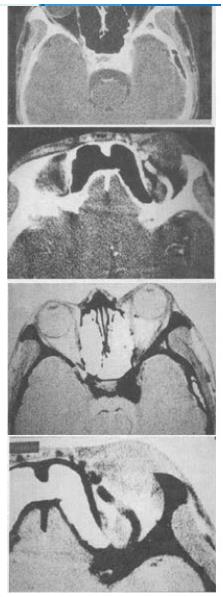

- 单项选择题 男,44岁,车祸伤及左侧眉弓和头部,半月后左眼球结膜高度水肿,视力减退,左眼球突出,CT检查如图,最可能的诊断为()。

- C